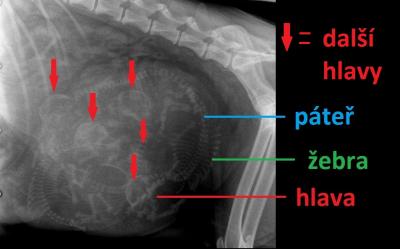

Rentgenologickým vyšetřením byla zjištěna přítomnost většího počtu štěňat v děloze, žádné štěně nebylo vzpříčené. Taktéž velikost kostřiček na RTG snímku neukazovala na přítomnost enormě velkého štěněte. Proto bylo rozhodnuto, že císařský řez ještě v tuto chvíli nutný není.

Atypický vývin těchto dvou štěňat byl pravděpodobně způsoben zaškrcením děložního rohu vaječníkovým vazem. Došlo tak nejspíše k snížení přívodu živin a ztížení odtoku žilní krve pupeční šňůrou. Edematózně prosáklé štěně má kostru normální velikosti, proto na RTG snímku nebylo možné odhalit přítomnost takto zvětšeného jedince. Toto štěně by nebylo schopno projít porodními cestami, proto byl v tomto případě císařský řez jediné možné východisko.